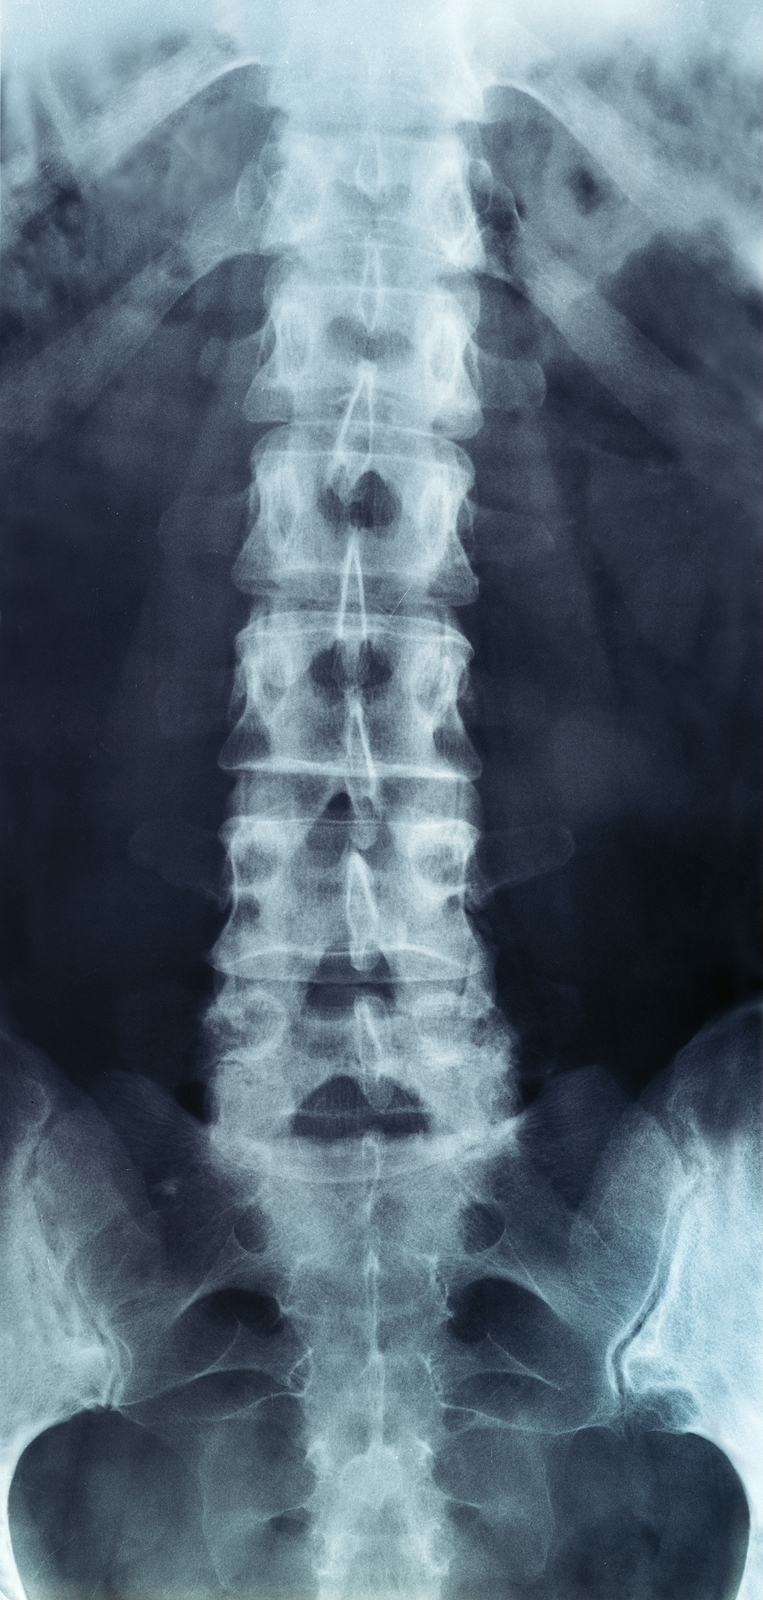

The human spine is made up of 24 spinal bones, called vertebrae, as well as the sacrum and the coccyx. The sacrum is a triangular bone near the bottom of the spine and the coccyx is more commonly known as the tailbone.

Vertebrae are stacked on top of one another to create the spinal column. The spinal column gives the body its form and helps sustain an upright position.

The lumbar spine—where pain is often experienced—is made up of five vertebrae positioned near the bottom of the spinal column. Doctors often refer to these vertebrae as levels L1, L2, L3, L4 and L5. The ‘L’ refers to ‘lumbar’. The lowest vertebra, L5, is connected to the top of the sacrum—a triangular bone at the base of the spine that is located between the two pelvic bones. Some people are born with an extra or sixth lumbar vertebra called L6. Having an extra vertebra doesn't usually cause physical problems.

X-rays are usually the first test ordered before any of the more specialized tests are completed. X-rays use electromagnetic radiation to show problems with bones and can also reveal problems such as fractures, infections, or bone tumors. X-rays of the spine can give your doctor information about bone alignment and can demonstrate how much degeneration has occurred in the spine. Both alignment and degeneration can affect the amount of space in the neural foramina and between the discs, which subsequently impacts the nerves in the area. This is important information your health care professional can use to establish a treatment plan.

Flexion and Extension X-rays

Special x-rays called flexion and extension x-rays may help to determine if there is true instability between vertebrae. These x-rays are taken from the side as you bend as far forward and then as far backward as you can. Comparing the two x-rays allows the doctor to see how much motion occurs between each spinal segment.